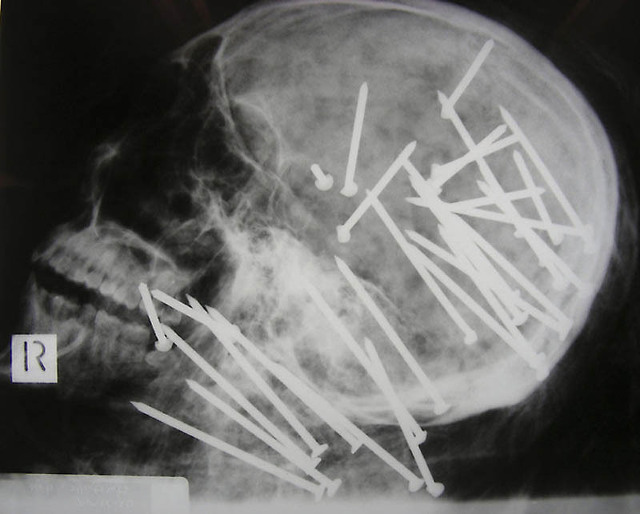

네일건을 맞은 중국인의 두개골